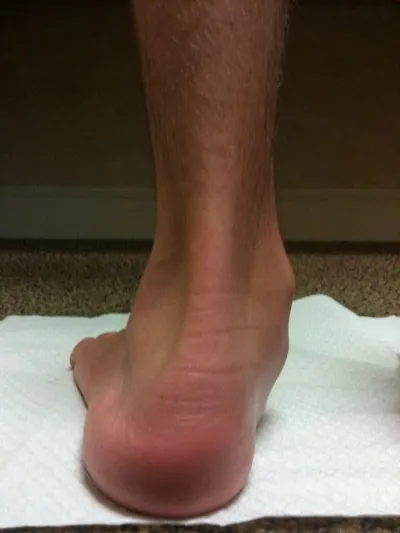

Below is a photograph of a patient before and after flat foot surgical correction with subtalar joint implant